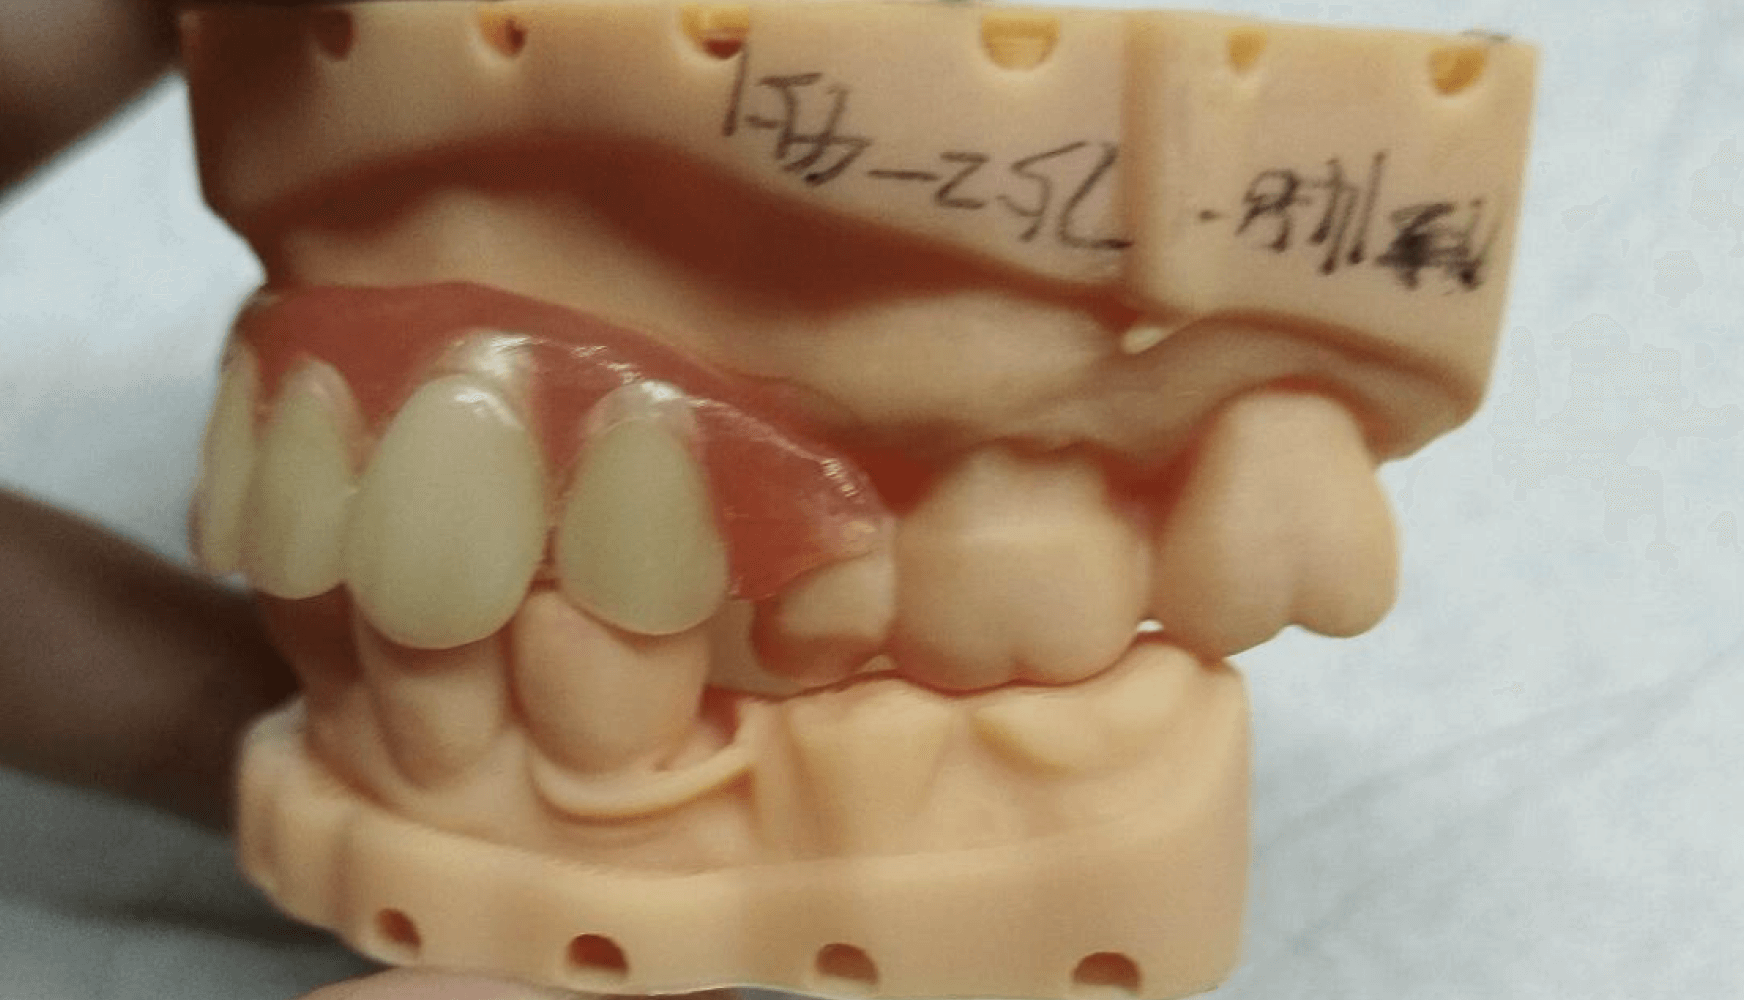

Figures 4a, 4b, 4c, 4d:

Figure 4a, 4b, 4c, 4d: The fabricated partial denture with its corresponding model. Both tissue shade and tooth shade met the patient’s expectations aesthetically and the overall clasping and fit did so as well.